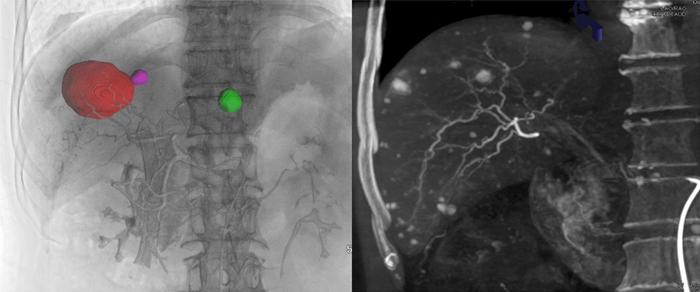

Application of Cone-beam Computed Tomography in Interventional Therapies for Liver Malignancy: A Consensus Statement by the Chinese College of Interventionalists (IMAGE)

Despite its crucial role in interventional therapies for liver malignancy, cone-beam computed tomography (CBCT) has not yet been fully integrated into clinical practice due to several complicating factors, including nonstandardized operations and limited recognition of CBCT among interventional radiologists. In response, the Chinese College of Interventionalists has released a consensus statement aimed at standardizing and promoting the application of CBCT in the interventional therapies for liver malignancy. This statement summarizes CBCT scanning techniques, and operational standards, and highlights its potential applications in clinical practice.